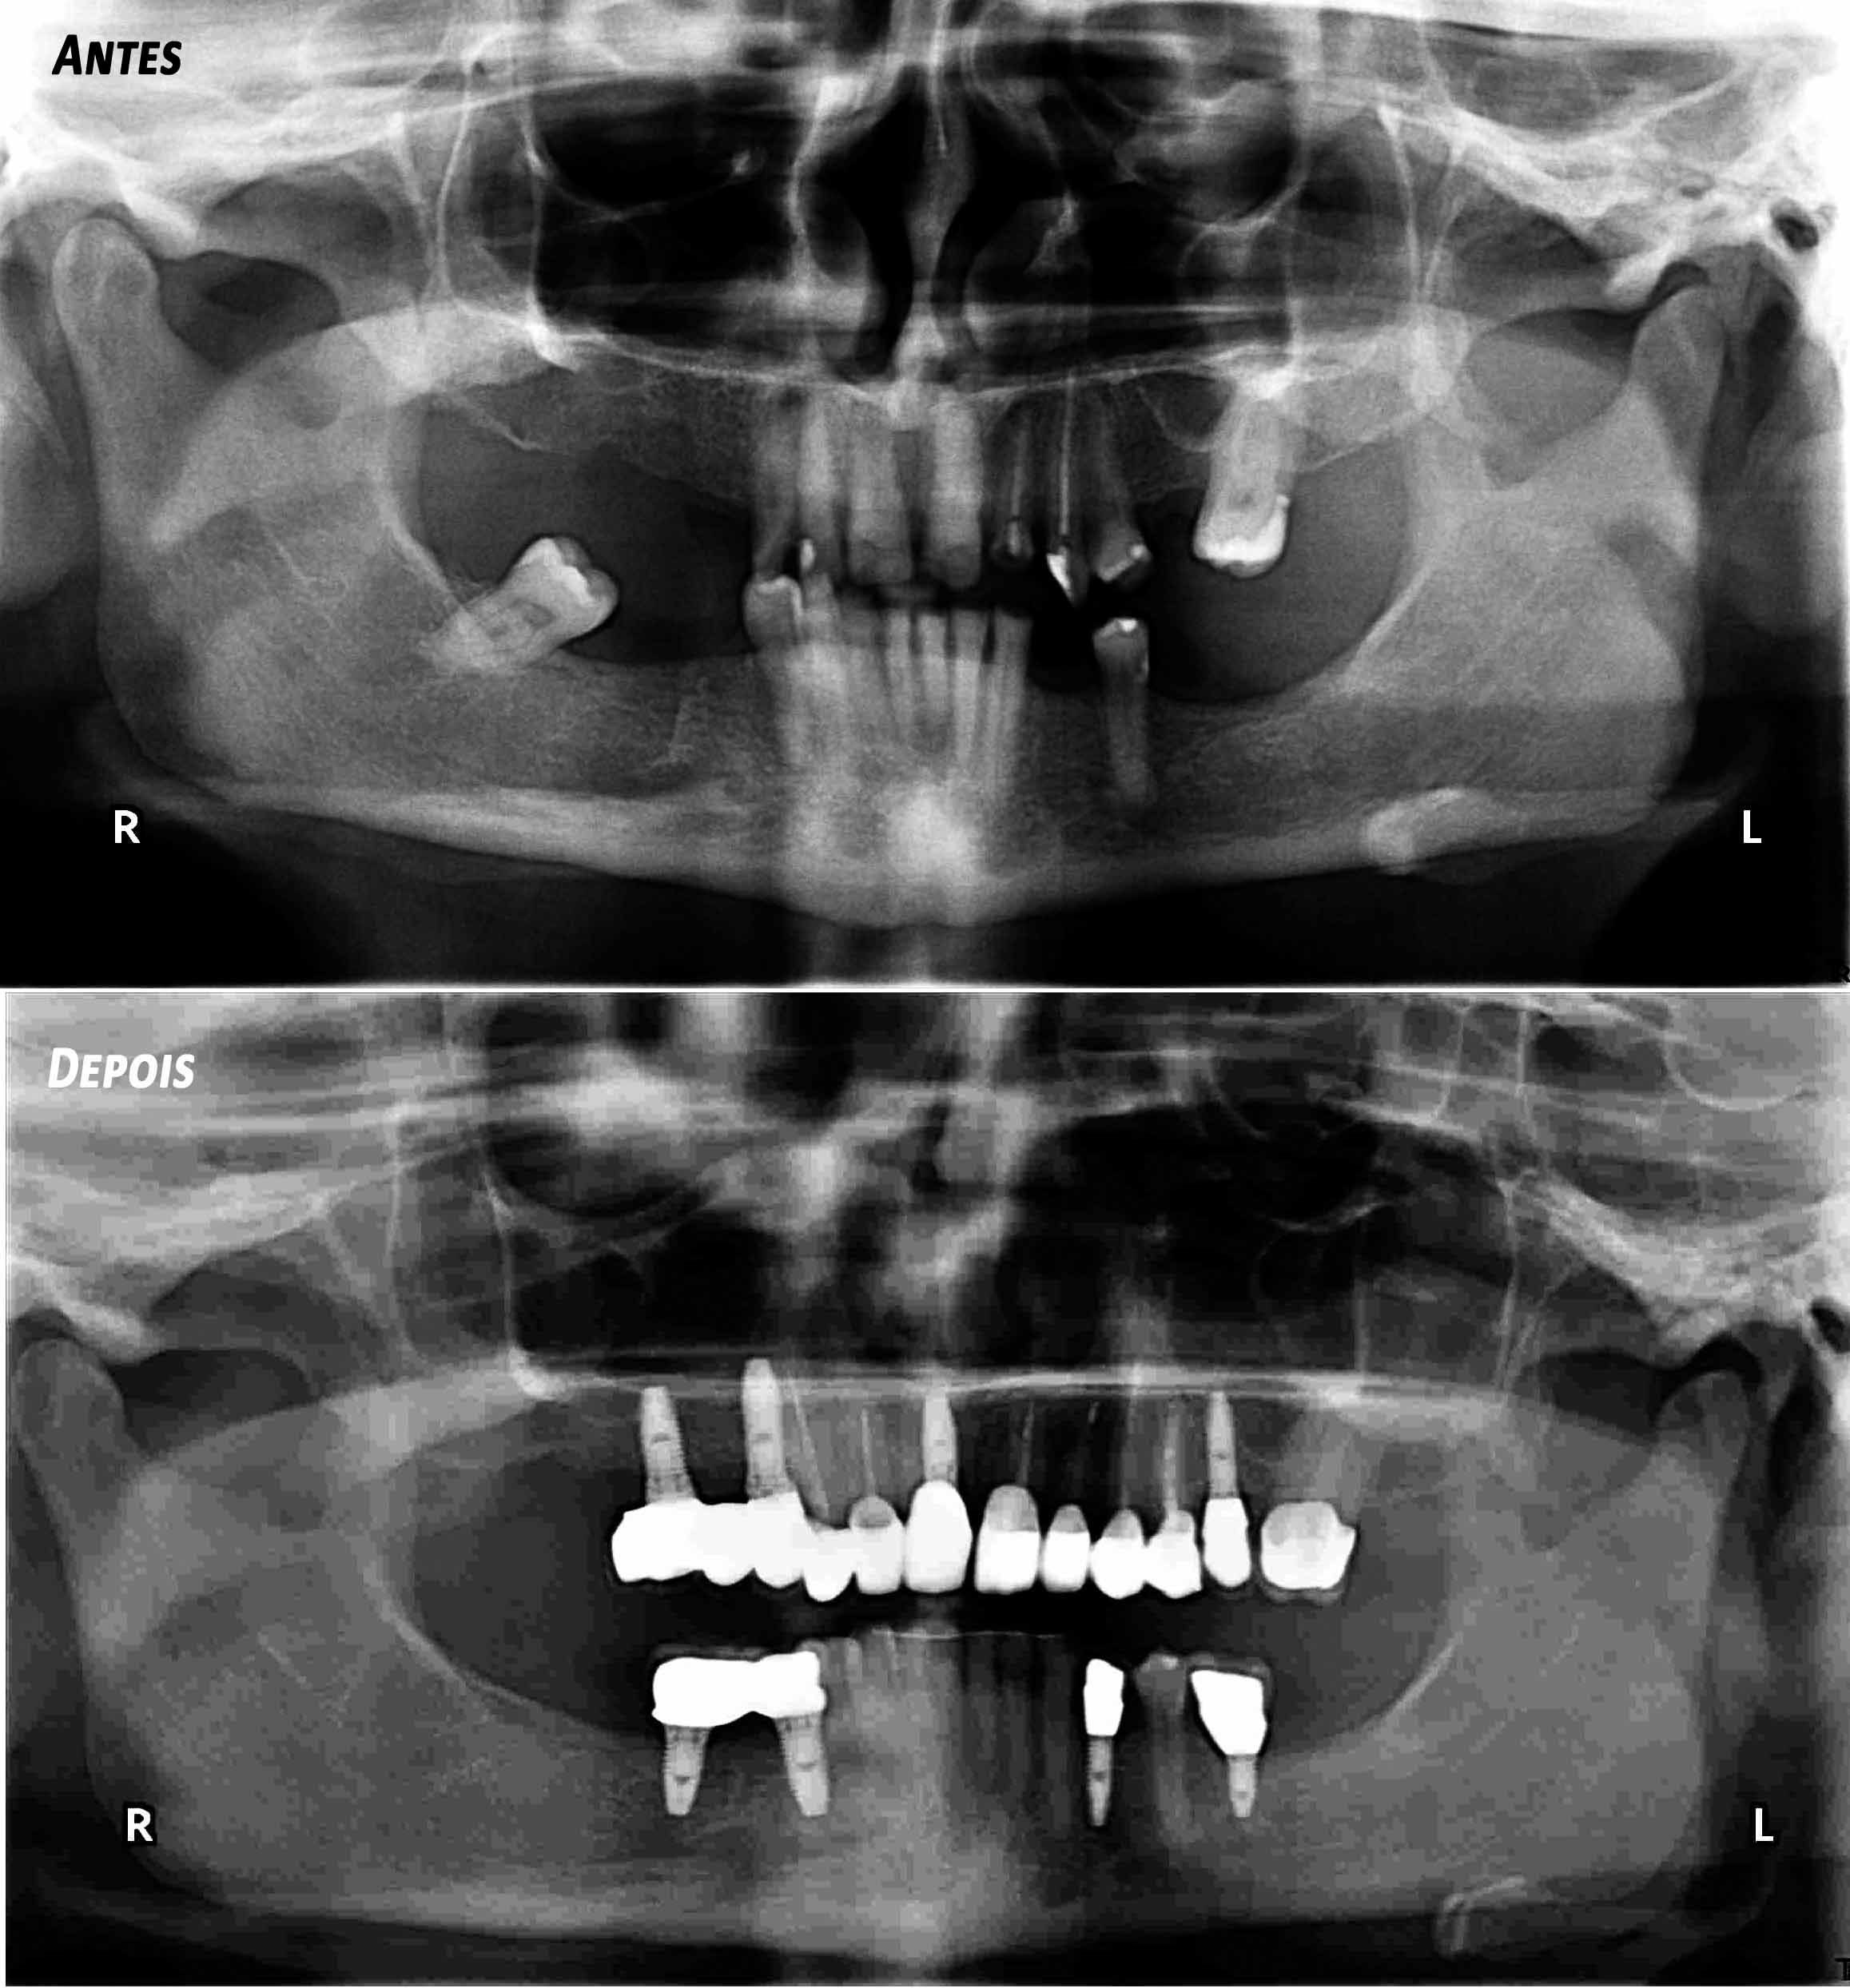

Ceramic Crowns over teeth and implants

Patient with limited functions and serious aesthetics problems.

Complex Rehabilitation – The Treatment:

The natural teeth that had a good prognosis were kept and the ones that needed their position changed were moved by a fixed orthodontic brace.

Afterward a surgery was made to place some implants. The treatment was finalized by placing the ceramic crowns over the implants and teeth.